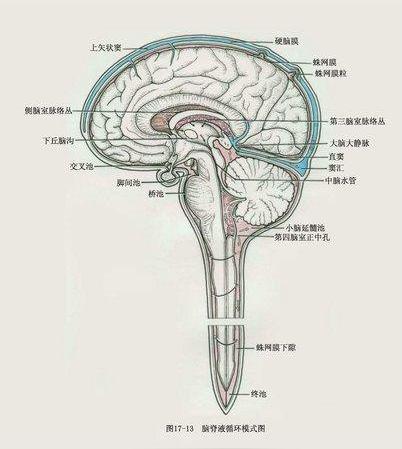

调节颅内压3.参与脑和脊髓的代谢4.维持正常ph